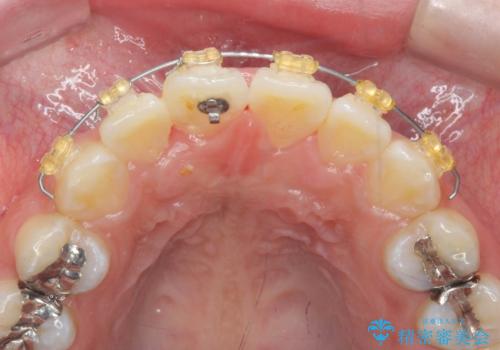

- 前歯の目立つねじれを矯正治療で治したい、と来院されました。

マウスピース矯正を始める前に、ねじれを取るのが短期間で済む部分ワイヤー小矯正を行うことで、全体的な治療期間を短くする治療計画を実行していきます。

前歯のねじれはマウスピース矯正の苦手な動きになり、治療期間が長くなる原因になりやすいです。